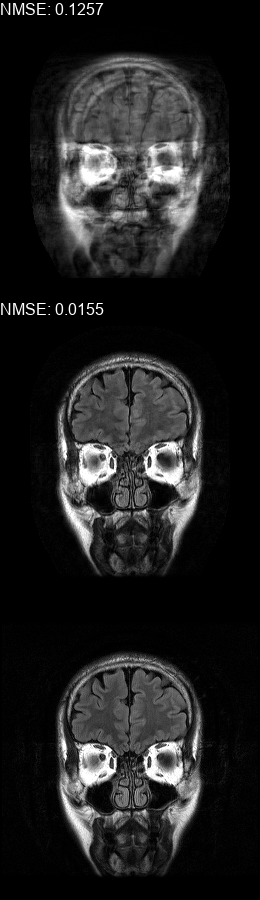

Fig. 5 contains four scan reconstructions from two patient cases. In both cases, the patient was requested to move at a certain time. In order to provide a ground truth for this scenario, another scan was performed using the same protocol for each patient, where the patient was required to hold still. The motion timing information for this case was obtained using the method described in [2] as it requires no additional hardware or changes to the scan protocol. We compare the reconstruction error using the SSIM [17] and the Visual Information Fidelity (VIF) [16] metrics, since a pixelwise comparison is not viable in this case.

Figure 5: Examples of real motion corrupted images together with their motion corrected counterparts. The bottom row shows a corresponding slice from a motion-free acquisition of the same subject. These motion-free images were acquired using an additional scan. The images on the top row are motion-corrupted. Images on the middle row were corrected using our method. (a,b) motion was was detected at t1=96subscript𝑡196t_{1}\!=\!96, (c,d) the motion was detected at t1=112subscript𝑡1112t_{1}\!=\!112. All scans were acquired using 𝒮260subscript𝒮260\mathcal{FS}_{260} presented in Fig. 1b.